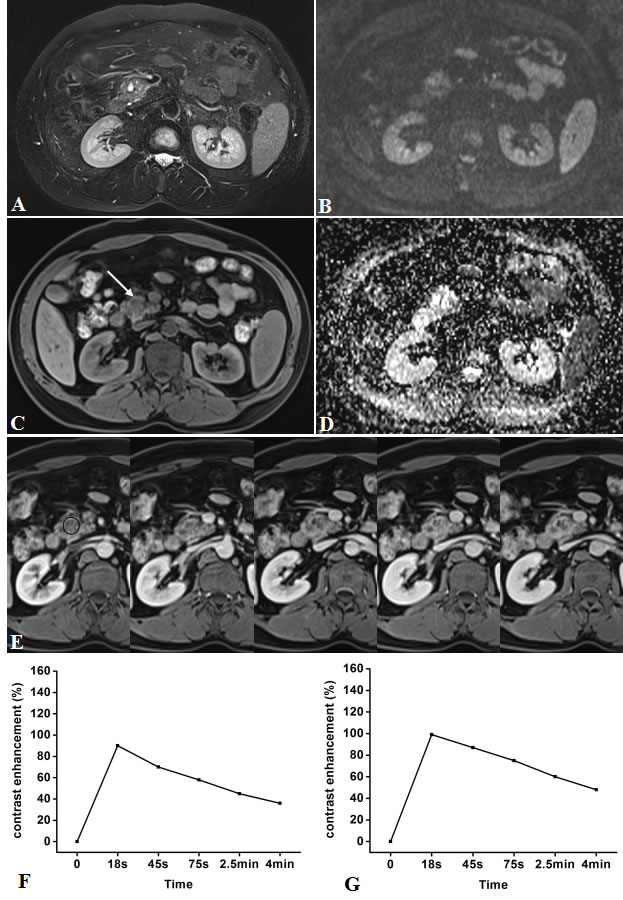

Figure 5: Representative pancreatic T2-weighted image (A), DWI with a b value of 600 s/mm2 (B), T1-weighted image (C), ADC map (D), DCE-MR images (E), and TIC profiles (F, G) in a 43-year-old man with mass-forming chronic focal pancreatitis in the head of pancreas (white arrow). DCE-MR images: 18s, 45s, 75s, 2.5 and 4min after contrast injection with constant gray scale. The ROIs of mass indicated with black circle and non-mass adjacent parenchyma (NAP) was located in pancreatic body. Pancreatic mass and NAP all demonstrates type-I a TIC which shows a rapidly increasing then gradually decreasing enhancement pattern. DWI shows pancreatic mass is clearly seen as isointense/mild-hyperintense with ill-defined margin.